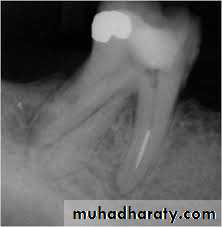

After determining the master apical file, the succeeding larger files are shortened by 0.5 or 1.0 mm increments from the previous file length.This step-back process creates a flared, tapering preparation while reducing procedural errors.

Step-back technique

MAF

WL – 0.5 mm

WL=21

SIZE=25WL=20.5

SIZE=30

WL=20

SIZE=35

WL=19.5

SIZE=40

WL=19

SIZE=45

WL=18.5

SIZE=50

WL=18

SIZE=55

WL=17.5

SIZE=60

WL=17

SIZE=70